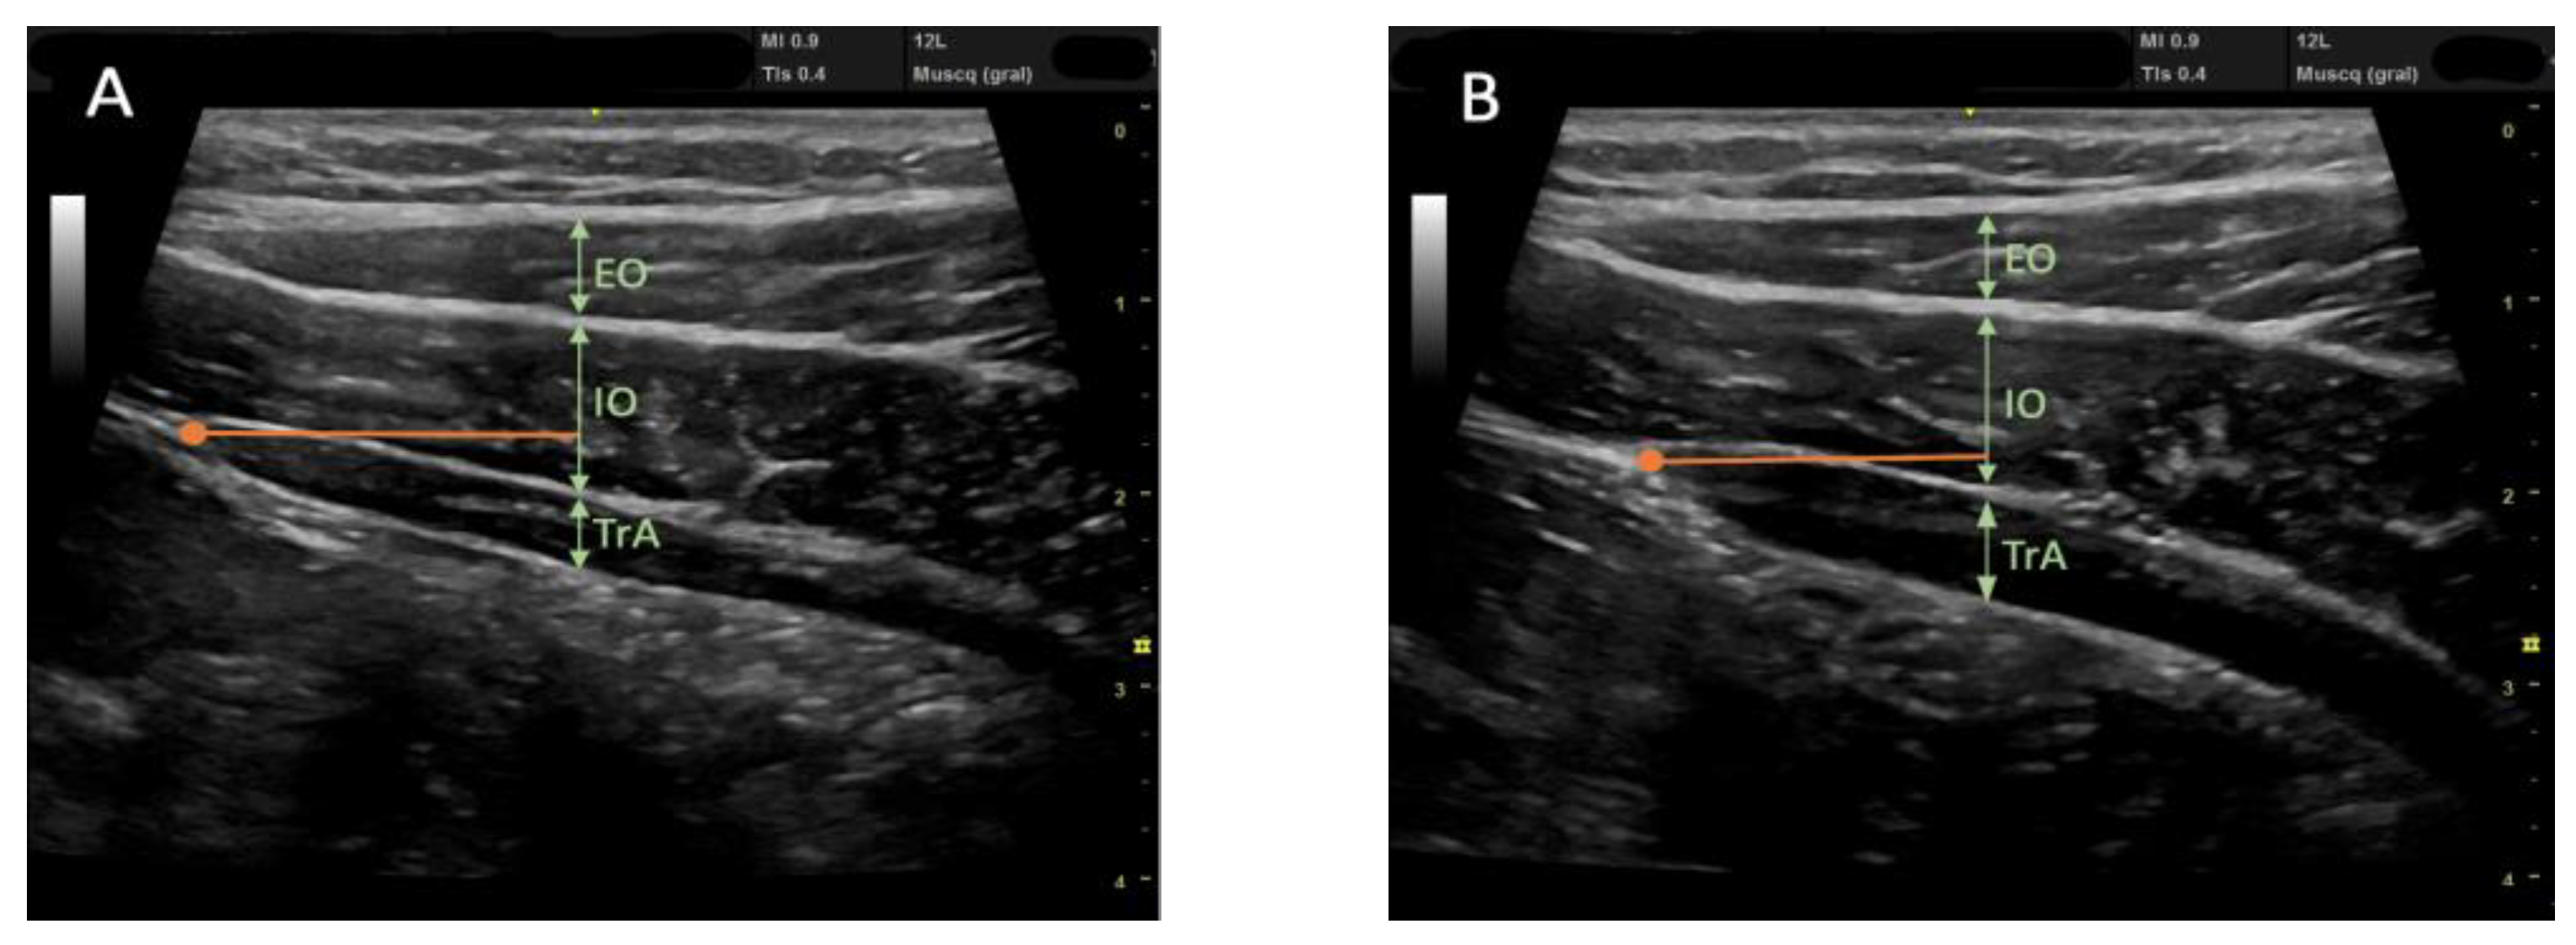

2.7. Ultrasound Protocol

2.8. Outcome Measurements/Descriptive Data